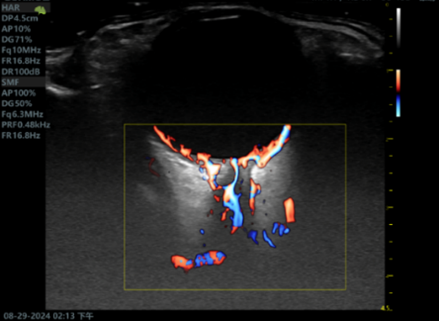

超声检查不仅能够直观的观察眼部病变形态结构,更是目前唯一能够反应眼部血管血流动力学的影像学检查方法。然而由于眼部血管分布密集表浅,普通超声检查的分辨力和敏感性无法满足精准诊断的临床需求。超微血流成像技术是一种新型的可以检测出高分辨率和最小伪影的小血管血流的检测方法,可以用于检测组织中缓慢和微弱的血流解剖。但对于视网膜动静脉栓塞,高血压、糖尿病等视网膜病变,肿瘤病变良恶性鉴别等仍存在不足。近年来随着超声造影技术的迅速发展,超声造影技术对微小血管和低流速、低流量血流信号具有更高的检出率,并且能更优质的显示组织血流的灌注特点。超声造影其独特的显像特点将在眼部占位,眼部血管性病变中取得更大的发展。将超声造影联合超微血流成像技术应用于眼底病变的观察可能为眼科疾病的诊断和鉴别诊断提供一种创新的融合显像检查方法。